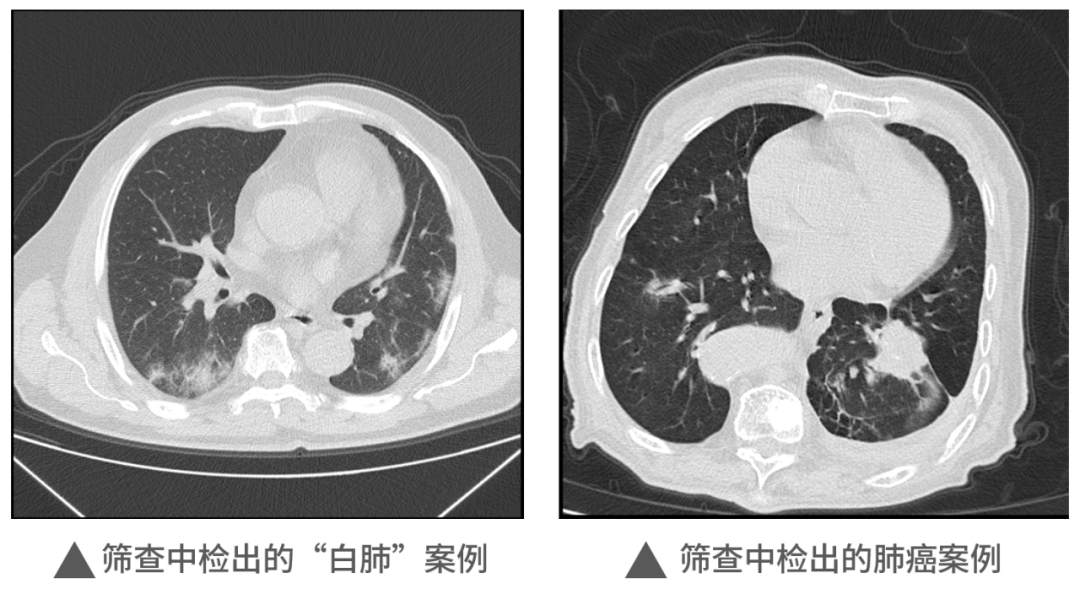

本次活動中,明峰醫(yī)療移動CT充分展現(xiàn)了它的適應性和便利性,在近1000人的檢查中,共查出肺部炎癥300余例,肺部結(jié)節(jié)560例,同時檢出一例肺癌病例。這對于本次篩查人員今后胸部健康和治療提供了重要的參考和指導,為全區(qū)居民和企業(yè)提供了堅實的保障,同時大大提升區(qū)內(nèi)的醫(yī)療健康保障能力。未來,明峰醫(yī)療醫(yī)療仍將持續(xù)致力于高端醫(yī)療設備的普惠應用。作為杭州市錢塘區(qū)的區(qū)內(nèi)企業(yè),將沿著區(qū)委區(qū)政府“四個全域”建設的發(fā)展規(guī)劃和區(qū)衛(wèi)健系統(tǒng)提出的目標及要求,發(fā)揮人才企業(yè)的優(yōu)勢,以科技創(chuàng)新引領企業(yè)發(fā)展,為區(qū)內(nèi)產(chǎn)城融合的服務配套做好應有的保障和支撐工作,探索政產(chǎn)學研合作的新思路新模式,共建共享,共同成長,造福更多的人民百姓,在書寫中國式現(xiàn)代化的錢塘答卷上也添上濃墨重彩的一筆。